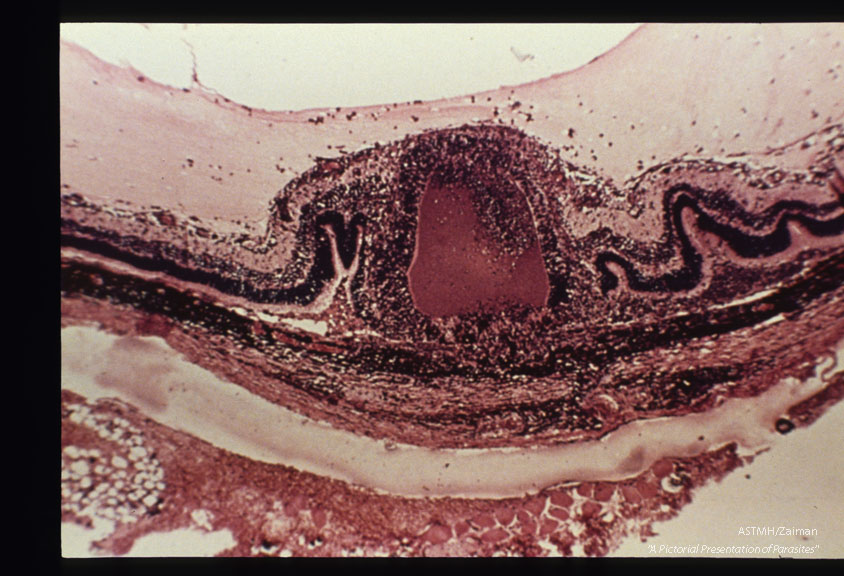

Detail of retinitis associated with cyst rupture, H&E stain.

Besnoitia jellisoni

Description: Detail of retinitis associated with cyst rupture, H&E stain.